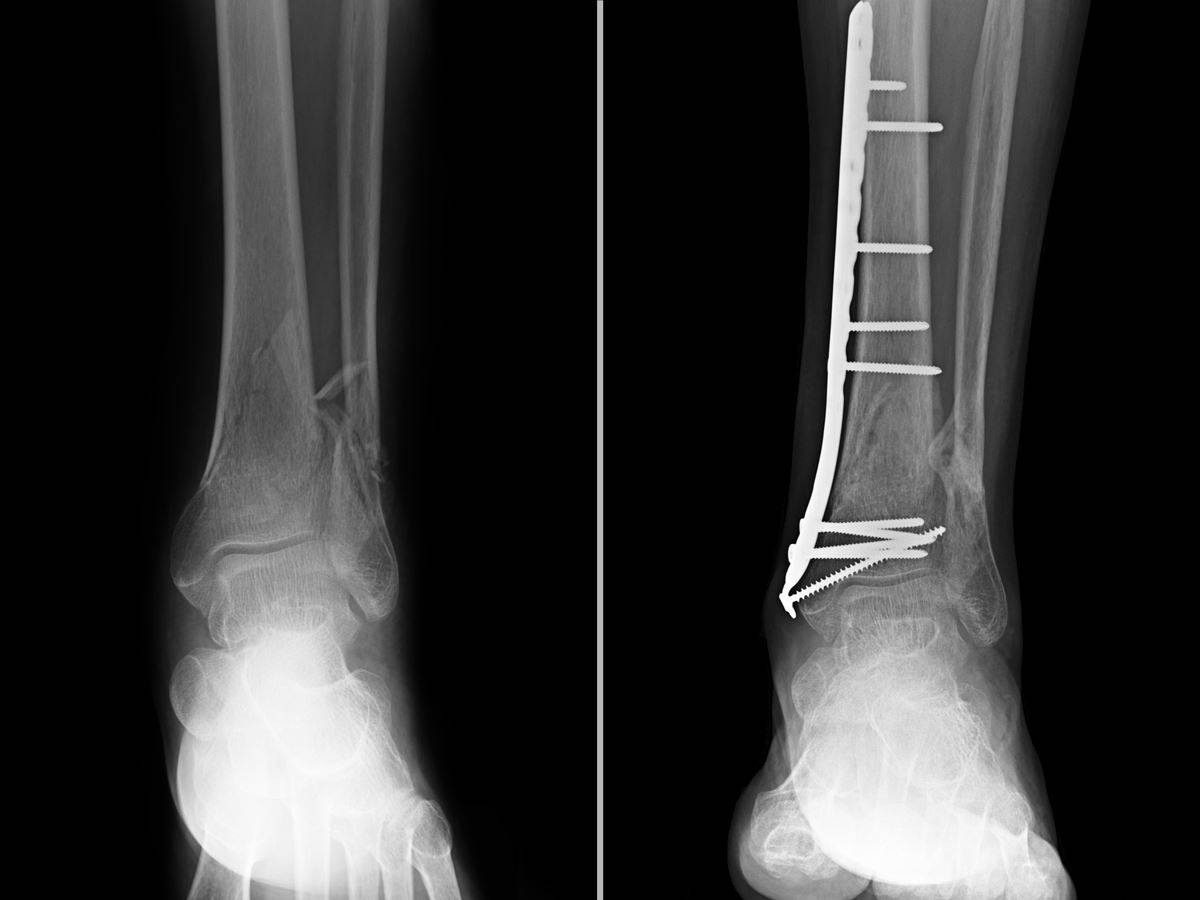

Bacaktaki kırıkları onarmak için fotoğrafta göründüğü gibi vida kullanılıyor. Hemşire üniversite hastanesinde vida bulunmadığı için dört gün ameliyat olamadı.

Dr. Ergün Demir ve Dr. Güray Kılıç, Sağlıkta Dönüşüm programı ile gelinen bu son noktada Türkiye’nin en köklü üniversite hastanelerinden birinde tıbbi malzeme (plak ve vida) eksikliği nedeniyle tibia kırığı (alt bacakta diz ile ayak arasında bulunan uzun kemik) gibi sıradan sayılabilecek ameliyatların yapılamayacak duruma geldiğini vurguladı.